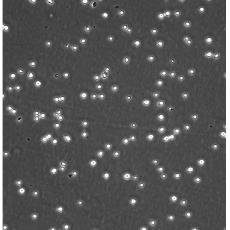

生長特性 suspension

形態(tài)特征 lymphoblast

細(xì)胞描述 CEM/C1是人T細(xì)胞白血病細(xì)胞株CCRF-CEM(見ATCC CCL-119)具有喜樹堿抗性的衍生株。1991年細(xì)胞株選擇并亞克隆了對CPT的抗性。細(xì)胞表現(xiàn)出對CPT類似物水溶性的托泊替康和非水溶性的9-氨基-CPT及10,11-亞甲二氧基-CPT具有交叉抗性。CEM/C1細(xì)胞對CPT的敏感性較母系CEM細(xì)胞低31倍。CEM/C1細(xì)胞表現(xiàn)非典型的多藥抗性和轉(zhuǎn)換拓補(bǔ)異構(gòu)酶I催化活性。對CPT的抗性維持6個月以上。